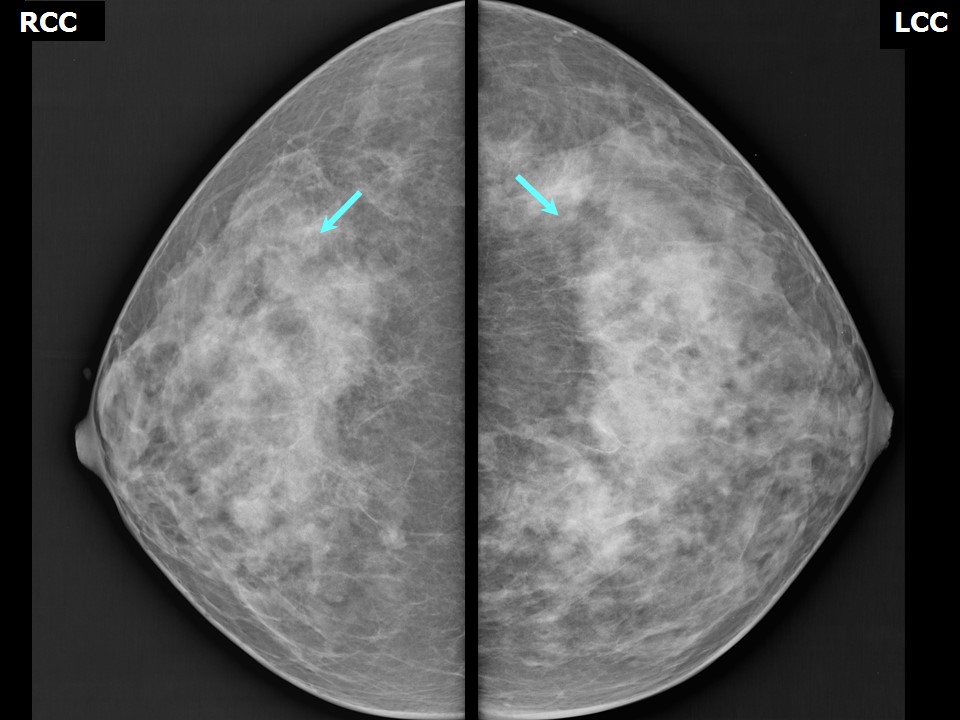

Аномалии молочной железы: медицинские примеры и визуализация

Раздел: Мудрость в деталях